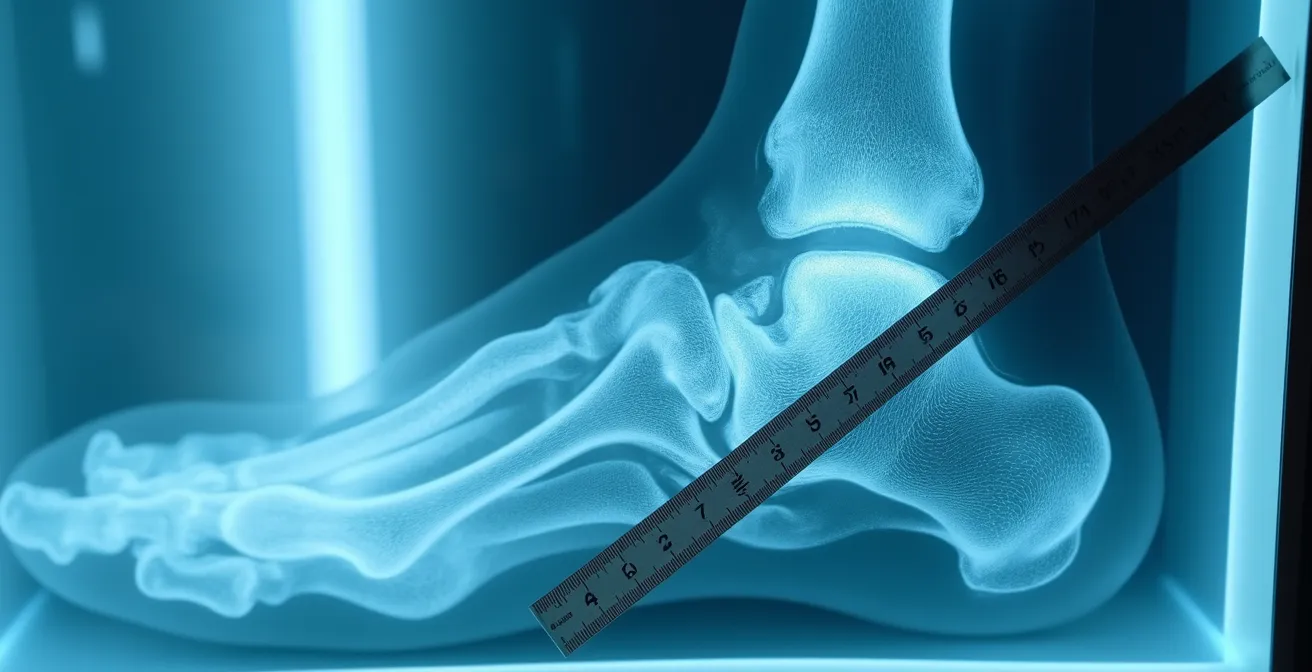

Contrairement à une approche standardisée, la sélection de la technique chirurgicale repose sur une évaluation biomécanique précise de votre pied. Trois paramètres fondamentaux orientent ce choix : l’angle de déformation mesuré par l’angle HVA (Hallux Valgus Angle), la mobilité de l’articulation métatarso-phalangienne, et la qualité osseuse évaluée par densitométrie.

L’angle HVA constitue le critère déterminant. Un angle HVA inférieur à 35° rend possible la chirurgie mini-invasive, tandis que les déformations plus sévères nécessitent des techniques ouvertes plus complexes. Cette distinction n’est pas arbitraire : elle correspond aux limites biomécaniques de correction possibles par voie percutanée.

Les examens pré-opératoires permettent de révéler précisément votre profil. Les radiographies en charge (debout) mesurent les angles réels sous contrainte. Le bilan podométrique analyse la répartition des pressions plantaires durant la marche. L’analyse de la démarche identifie les compensations posturales qui pourraient compromettre les résultats. Cette évaluation complète transforme une décision générique en stratégie personnalisée, adaptée à vos caractéristiques anatomiques et fonctionnelles spécifiques.